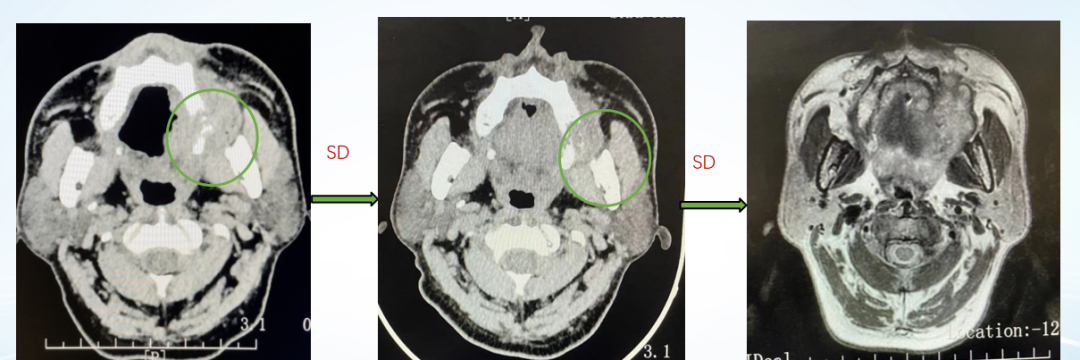

影像学评估:

图22、呋喹替尼治疗期间,患者肺部转移灶胸部增强CT评估情况:左(2020-10-23)、中(2021-05-27)、右(2021-07-06)

图23、呋喹替尼治疗期间,患者口腔颊黏膜转移灶口腔增强CT评估情况:左(2020-10-23)、中(2021-05-27)、右(2021-07-08)

疾病进展:2021年8月,患者出现咳胸闷,咳嗽。胸部CT提示双肺转移瘤相仿,右侧支气管内多发软组织密度影。

图24、胸部增强CT显示支气管内新增转移病灶:左(2021-07-06)、右(2021-08-31)